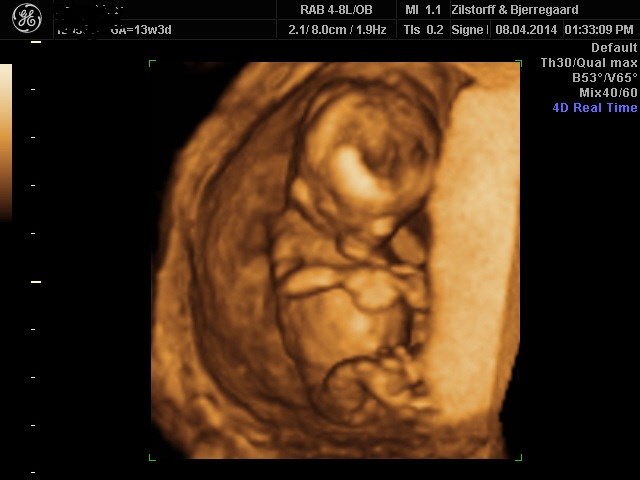

Han har det rigtig godt derinde og alt er som det skal være. Hun gennemscannede hjertet og det så også bare helt perfekt ud. Så efter flere måneders bekymringer kan jeg laaaaaangt om længe nyde graviditeten

Terminen blev rykket og er nu den 10 okt frem for den 11

Og i skal ikke snydes for et lille billede, selvom det ser lidt uhyggeligt ud